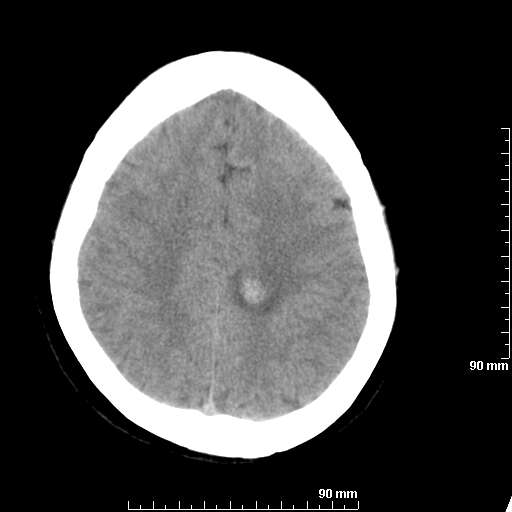

我院西门子单排CT由于一零件受损而产生的伪影.

哈哈,都不是。是虑线器fiter裂损。大家没想到吧。

哦,跟脑出血有点像哦

形状不规则,边缘模糊。比较特殊的一种伪影哈!

这种伪影很常见!伪影应该是在视野的中心的。

西门子的虑线器fiter裂损这才是很难见的问题,GE的最常见

虑线器老化,中间崩裂一块掉了